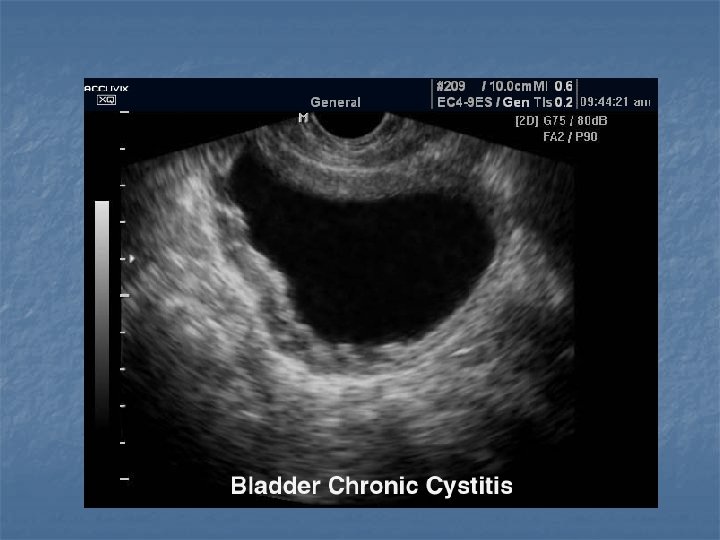

Bladder